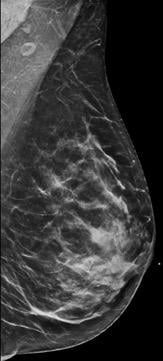

Breast density is divided into four categories, from lowest to highest amounts of fibroglandular tissue composition. Category A: Almost entirely fatty (least amount of fibroglandular tissue). Category B: Scattered fibroglandular tissue. Category C: Heterogeneously dense. Category D: Extremely dense (most amount of fibroglandular tissue).

Breast tissue is composed of a mixture of milk ducts, glands and supportive tissue, which is collectively called fibroglandular tissue and fat. The radiologist who reviews the mammogram analyzes overall breast density, which is the ratio of the amount of fibroglandular tissue to fatty tissue. Women with dense breasts have more fibroglandular tissue than fatty tissue. Fibroglandular tissue appears white on a mammogram and fat appears black. It becomes harder to detect a white cancer against a white background — imagine trying to find a polar bear in a blizzard. Dense tissue is harder to see through to detect abnormal findings. As breast density increases, cancer detection becomes more difficult. Additionally, breast cancer risk rises with increasing breast density. Multiple studies have indicated that there is a two- to six-fold increased risk of breast cancer for a woman who has an extremely dense breast versus a woman with an almost entirely fatty breast.4

Breast density is divided into four categories, from lowest to highest amounts of fibroglandular tissue composition:

Category A: Almost entirely fatty (least amount of fibroglandular tissue)

Category B: Scattered fibroglandular tissue

Category C: Heterogeneously dense

Category D: Extremely dense (most amount of fibroglandular tissue)